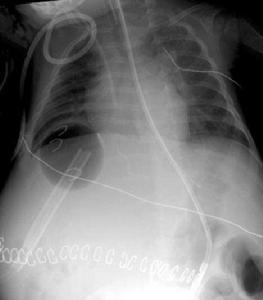

⑸腔靜脈造影:經上、下肢淺靜脈插管進行下腔靜脈對端造影,可確定下腔靜脈有無梗阻,阻塞部位,範圍,程度,同時可進行腔靜脈測壓及肝靜脈造影。腔靜脈造影與二維超聲檢查結合,可確定下腔靜脈阻塞的性質,部位,範圍,程度,同時確定肝靜脈與下腔靜脈有無交通及交通的程度。腔靜脈造影不僅能進一步明確診斷且能為選擇手術治療方案提供依據。

影像學檢查下腔靜脈造影可獲確診,都卜勒檢查可發現梗阻以上靜脈擴張。